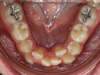

L'encombrement chez l'adolescent

Manque de place :

(encombrement - dysharmonie dento-maxillaire)